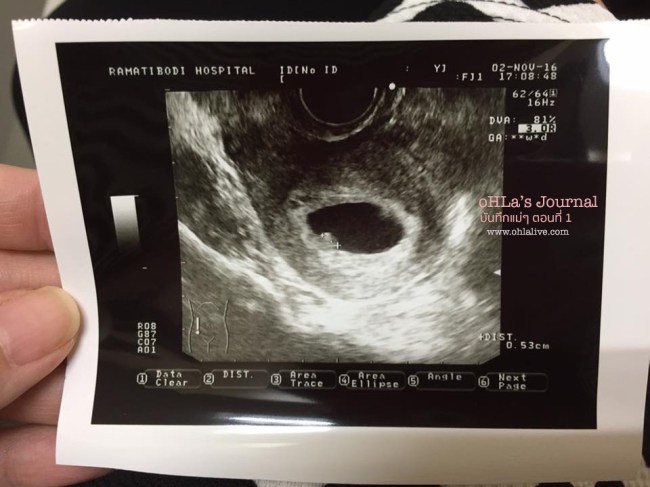

ภาพอัลตราซาวน์ครั้งแรก อายุครรภ์ 6 สัปดาห์